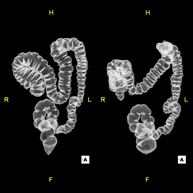

- Colonoscopia virtual  La colonoscopia virtual es una técnica no invasiva que permite la visualización tridimensional y bidimensional del intestino grueso o del colon mediante la toma secuencial de imágenes captadas con TC Multidetector de última generación. La calidad de las imágenes permite la navegación virtual por el interior del recto y del colon gracias al procesamiento en estaciones de trabajo especializadas. La preparación de la prueba consiste en realizar una dieta baja en fibra tres días antes de la prueba (para limpiar el colon y el recto) y de la ingestión de contraste oral yodado el día antes de la prueba (para marcar las heces y poder distinguirlas correctamente de las posibles lesiones colónicas). A diferencia de la fibrocolonoscopia, no se requiere sedación ni soluciones evacuantes. La prueba se realiza en la sala del TC donde, a través de un pequeño tubo flexible, se insufla aire para distender el colon. La colonoscopia virtual es una técnica no invasiva que permite la visualización tridimensional y bidimensional del intestino grueso o del colon mediante la toma secuencial de imágenes captadas con TC Multidetector de última generación. La calidad de las imágenes permite la navegación virtual por el interior del recto y del colon gracias al procesamiento en estaciones de trabajo especializadas. La preparación de la prueba consiste en realizar una dieta baja en fibra tres días antes de la prueba (para limpiar el colon y el recto) y de la ingestión de contraste oral yodado el día antes de la prueba (para marcar las heces y poder distinguirlas correctamente de las posibles lesiones colónicas). A diferencia de la fibrocolonoscopia, no se requiere sedación ni soluciones evacuantes. La prueba se realiza en la sala del TC donde, a través de un pequeño tubo flexible, se insufla aire para distender el colon.